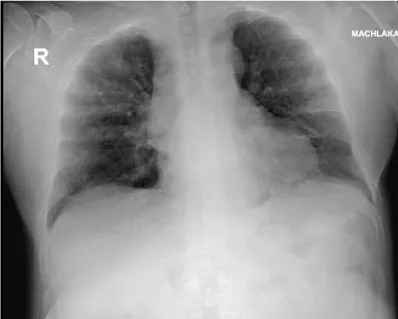

The patient was exposed to a verified positive COVID-19 subject on March 18, 2020 and 4 days later he was tested and found positive for COVID-19 PCR. On admission the patient had fatigue, dry cough and mild dyspnea. He ruled out diarrhea, chills or chest pain. Physical examination revealed normal body temperature of 37.6°C, heart rate 64 beats/minute, respiratory rate 19 breaths/minute and 96% O2 saturation measured in room air (Figure 3). Blood pressure measurement was 121/60 mmHg. Chest x-ray on arrival showed bilateral increased interstitial markings, with no consolidation or pleural effusion (Figure 4). On arrival the patient was categorized as a moderate disease patient.